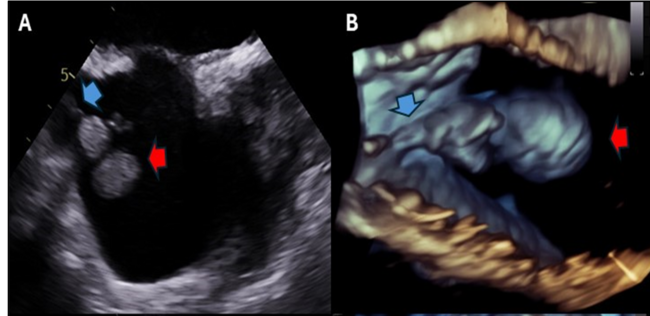

A 59-year-old man with heart failure with reduced ejection fraction (HFrEF) and a single-chamber implantable cardioverter-defibrillator presented with group B streptococcus bacteremia. Transesophageal echocardiography (TEE) revealed a 2.4 x 1.5-cm vegetation on the atrial portion of the right ventricular lead (Figure A and B). Due to the embolization risk with extraction alone, percutaneous mechanical aspiration (PMA) using the AngioVac system (AngioDynamics) was pursued. The AngioVac system, consisting of aspiration cannulas connected to a veno-venous perfusion circuit, was inserted via the right internal jugular vein. Under TEE guidance, the aspiration catheter removed the vegetation (Figure C-F) and then repositioned to capture residual vegetative material. The lead was successfully extracted and pathology confirmed infection (Figure G and H). For CIED vegetations, percutaneous mechanical aspiration followed by extraction may reduce embolization risk.